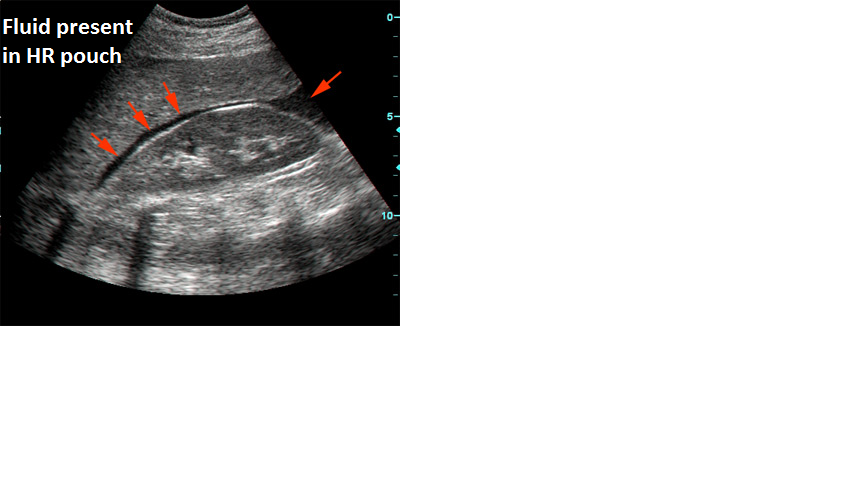

Summary of Hepato-renal recess/ Pouch of Morison

Hepato-renal recess/ Pouch of Morison

The hepatorenal recess[1] (subhepatic recesspouch of Morison or Morison's pouch) is the space that separates the liver from the right kidney. As a potential space, the recess is not filled with fluid under normal conditions.

However, fluid can collect in this space in circumstances where the abdomen fills with fluid, such as mostly ascites and hemo peritoneum. This fluid may be seen on ultrasound or computed tomography (CT scan).

The intraperitoneal fluid, be it blood, ascites, or dialysis, collects in this space and may be visualized, most commonly via ultrasound or computed tomography (CT) scanning. As little as 30 or 40 ml of fluid in the abdominal cavity may be visualized in this space.

Early visualization of fluid in the hepatorenal recess on FAST scan may be an indication for urgent laparotomy